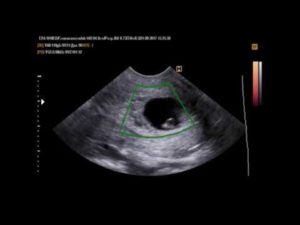

Во время ультразвукового исследования врач может обнаружить замершую беременность. Этот метод считается «золотым» стандартом при диагностике данной патологии. Отсутствие сердцебиений и отставание плода в размерах – главные симптомы замершей беременности при УЗИ.

• УЗИ: покажет прекращение сердцебиения плода. Не паникуйте раньше времени, если врач не услышал сердцебиение плода через стетоскоп — такое возможно при переднем расположении плаценты или наличии жировой прослойки на брюшной стенке;

Если при ультразвуковом исследовании диагностирована замершая беременность, видео «показывает» отсутствие сердцебиения у плода.